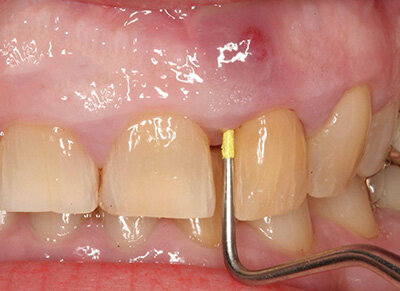

В десне гной может накапливаться из-за того, что там развивается пародонтальный абсцесс. Здесь будет появляться гной, выделяться кровь из зуба, рядом с которым произошел нарыв. Кроме того, зуб будет ныть и болеть. К нагноению может привести пародонтоз, его развитие либо кариес, которые не лечили вовремя.

Если у вас появились гнойные выделения из десны, есть прыщ, внутри которого накапливается гной, ощущается боль, зубы ноют, тогда не стоит медлить, а сразу же идти к врачу. Если запустить гнойное воспаление, которое образовалось в десне, то могут возникнуть серьезные последствия. Все это может дойти даже до заражения крови.

Что касается гнойного прыща, то он может иметь любой размер. У некоторых он может напоминать по форме горошину, а иногда может достигать размера половины грецкого ореха. Но стоит знать, что нельзя судить о серьезности проблемы по размерам этого прыща. Если имеется гнойный прыщ и он небольшой, то при отсутствии лечения за день он может значительно увеличиться.

Изначально человек не страдает из-за того, что образовалось небольшое нагноение. Боль может возникать, когда он кушает, может появляться кровотечение, когда чистит зубы либо выделяться гной, если надавить на корень зуба. Позже в десне становится все больше гноя, что приводит к распространению инфекции. Если отсутствует необходимое лечение, то может начинаться выпадение здоровых зубов.

Когда заболевание только начинается, гной накапливается в одном зубе, но спустя время, может пойти по другим зубам и приобрести форму хронического пародонтоза. Поэтому, как только вы увидели нагноение, отправляйтесь к специалисту и проконсультируйтесь с ним.